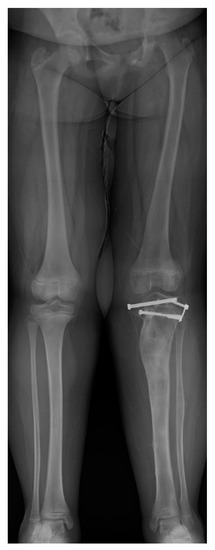

11. Hemi-Epiphysiodesis

12. Physeal Arrest Resection